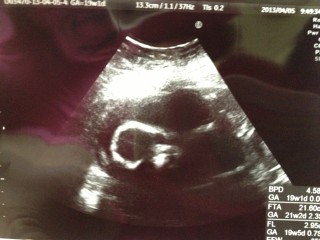

下からみた(足とお尻)エコーです(*´∀`*) 先生に「性別知りたい?」と聞かれ「知りたいです!」と言うと「女の子だね」と言われ確定しました。 動くたびに愛しく思え、にやけがとまりまけんでした(笑)

何が写ってるのかサッパリですが(笑)頭部らしいです。 推定体重350gで、性別は男の子のようです!

エコーをあててすぐにシンボルが見えました(^^) エコー中はバンザイしたり手を降ったり元気に動いてました。 次回は4Dエコーです!